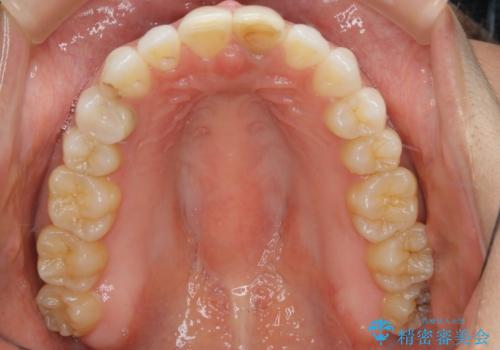

すきっ歯を治したい。インビザライン・ライトによる矯正治療

- 正中離開を気にされて来院された患者様です。

インビザラインでの治療を希望され、正中離開のみ治したいとのことだったので、インビザライン・ライト(片顎)での治療を選択しました。